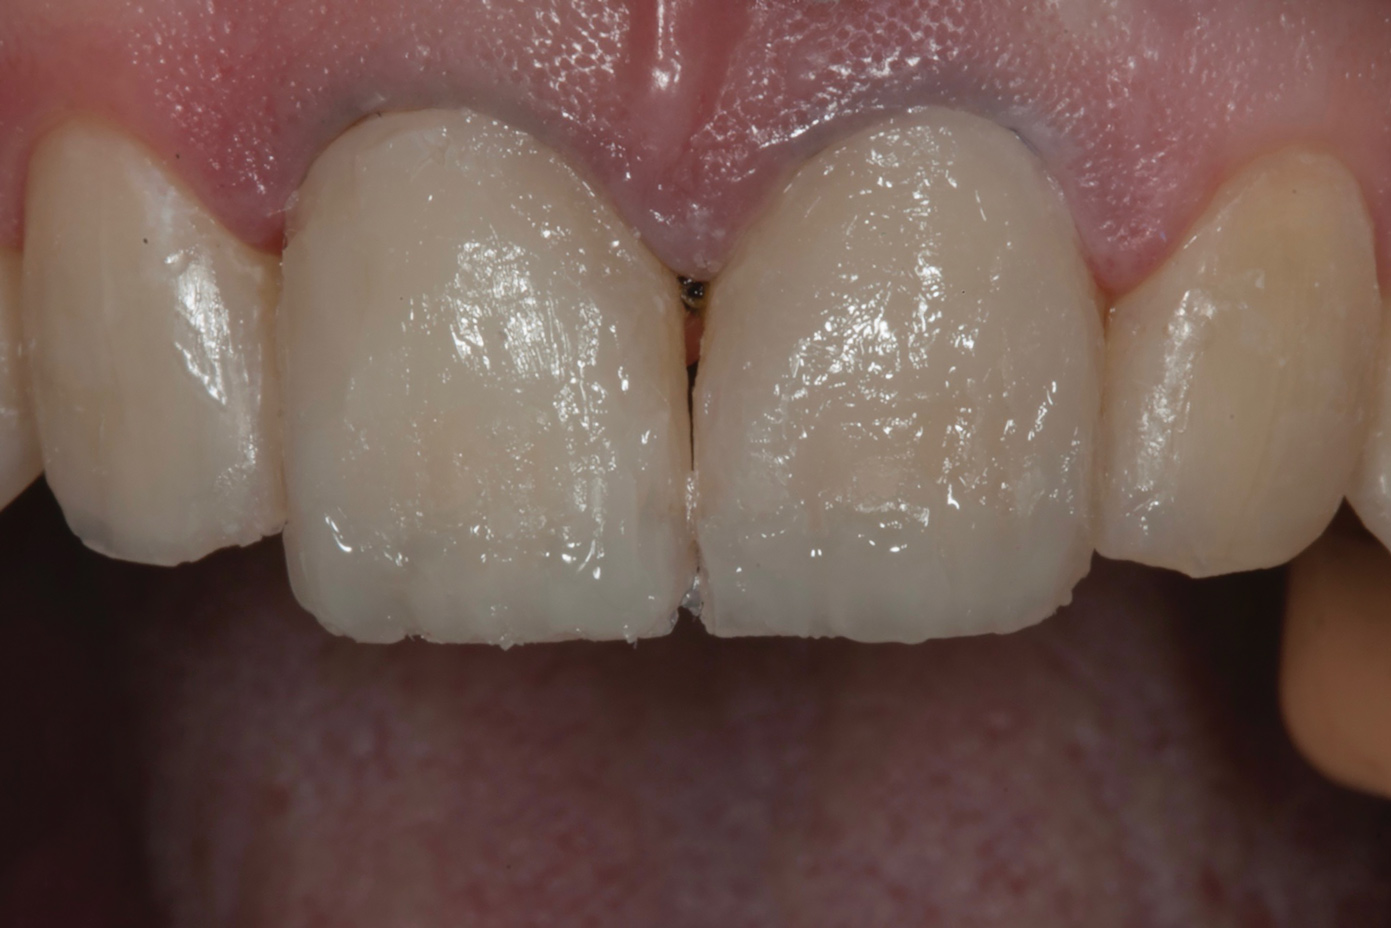

A 34-year-old male patient with no medical issues presented to the office with the chief complaint of a failing crown on tooth No. 12. The patient was also unhappy with his bite and the appearance of his teeth (Figure 1 and Figure 2).

A comprehensive examination was carried out, and preoperative photographs were taken (Figure 1 through Figure 4). The patient presented with fair oral hygiene and slight, generalized tissue inflammation. Caries and defective restorations were detected on teeth Nos. 4, 5, 13, and 14. The crown on tooth No. 12 was showing signs of leakage, and although the endodontic access cavity had been temporarily restored with composite, this endodontic re-treatment was acceptable and the tooth was otherwise symptom-free. Erosion was present on most of the posterior teeth and the cuspids, and abrasion was noted on teeth Nos. 4, 5, 10, 11, 20, 21, 22, 28, and 29. An examination of the patient's muscles, joints, and bite revealed no joint sounds, a normal range of motion, and negative joint load and immobilization tests.

The dentofacial examination revealed a low smile line with no incisor display when the lips were in repose. The anterior teeth were chipped and worn, and their overall color was darkened. The buccal corridors were deficient, and the failing crown on tooth No. 12 was visible in a full smile.

Fig 1. Preoperative smile photograph.

Figure 1